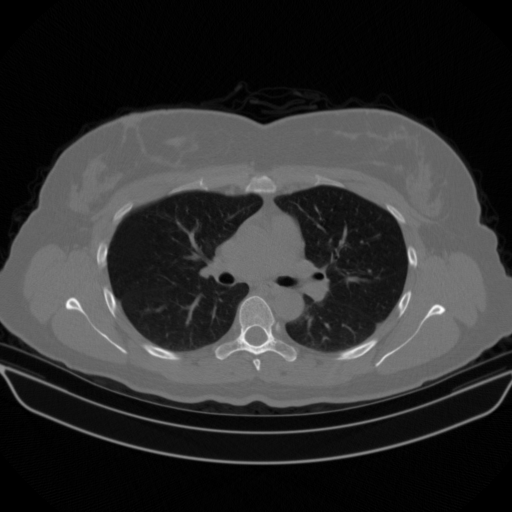

Original VENOUS CT scan

No window - Raw intensity values

Lung window (WL -600, WW 1500 β†’ Low βˆ’1350, High +150)

Mediastinum window (WL 40, WW 400 β†’ Low βˆ’160, High +240)